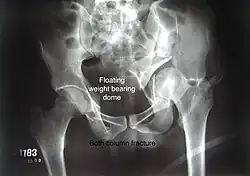

Both column fracture showing floating weight bearing dome -

Both column fracture after fixation with screws and plates -

Combined both column fractures | These are the most complex injuries. Here the weight bearing roof or dome of the acetabulum is a floating piece. This adds to complexity of management.

All three x-ray views plus CT scan is a must for diagnosis and management of this complex injury.

Like any other acetabular fracture, if the femoral head is dislocated out of the socket, early reduction into socket is a priority. However, in this injury, non-operative treatment rarely gives satisfactory results. Surgical management is ideal. The choice of approach rests with the surgeon, but going from front, or anterior approach is must. The posterior injury may be tacked with anterior approach by experienced surgeon. If the patient is unfit to undergo major surgery due to any reason, longitudinal traction to achieve secondary congruence of hip may help to restore hip function, though partially. |